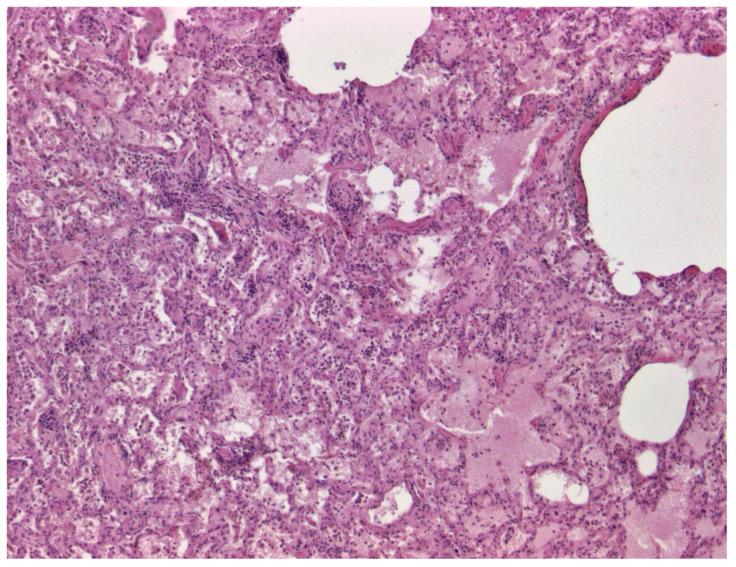

The first official case of bluetongue virus serotype 3 (BTV-3) in Portugal was confirmed in sheep from the district of Évora in September 2024. Notably, mortality was observed in pregnant sheepdogs within the affected sheep flocks. This study presents four cases of pregnant dogs infected with BTV-3 in mid-September 2024, all of which aborted prior to death. BTV-3 was identified by RT-qPCR following initial positive results from pan-BTV RT-qPCR. The virus was subsequently isolated from the blood of one of the dogs in BHK-21 cells, and a partial sequence of the vp2 gene was obtained. This sequence showed 100% similarity to sheep BTV3/3234/PT2024, identified in Portugal in September 2024, as well as to BTV-3/NET2023, first reported in the Netherlands in 2023. These findings suggest that the viruses may be related or share a common origin. Co-infection with common canine viruses and pathogenic bacteria was ruled out, confirming that the fatalities were due to BTV-3 infection, probably by ingestion of sheep placenta after lambing. Our results confirm the potential for the transmission of BTV-3 to non-ruminant species, particularly carnivores, and, therefore, the wider ecological implications of this virus. In addition, the identification of transplacental transmission of BTV-3 in one of the dogs provides new evidence highlighting the complexity of the virus' transmission mechanisms.

2024年9月,葡萄牙埃武拉区的绵羊中确诊了该国首例蓝舌病病毒3型(BTV-3)官方病例。值得注意的是,在受影响的羊群中,怀孕的牧羊犬出现了死亡情况。本研究介绍了2024年9月中旬感染BTV-3的4例怀孕犬病例,所有病例均在死亡前流产。在泛BTV RT-qPCR初步检测结果呈阳性后,通过RT-qPCR鉴定出BTV-3。随后从其中一只犬的血液中在BHK-21细胞中分离出该病毒,并获得了vp2基因的部分序列。该序列与2024年9月在葡萄牙鉴定的绵羊BTV3/3234/PT2024以及2023年首次在荷兰报道的BTV-3/NET2023显示出100%的相似性。这些发现表明这些病毒可能相关或有共同起源。排除了与常见犬病毒和病原菌的共同感染,证实死亡是由于BTV-3感染,可能是在母羊产羔后摄入了羊胎盘所致。我们的结果证实了BTV-3传播给非反刍动物物种,特别是食肉动物的可能性,因此也证实了这种病毒更广泛的生态影响。此外,在其中一只犬中鉴定出BTV-3的经胎盘传播,为突出该病毒传播机制的复杂性提供了新证据。